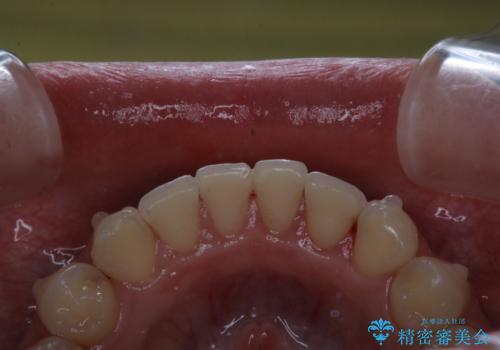

インビザライン中にステインの除去

- インビザラインでのマウスピース矯正中の方で、歯の表面のステインをきれいに取りたいとのことでした。PMTC60分コースを行いました。

PMTC(保険外治療)は、毎日の歯磨きで落としきれない汚れや、コーヒ、紅茶・タバコのヤニなどの着色も除去します。目には見えない歯と歯の間・歯肉の境目・インビザライン中はアタッチメント周囲などに残っているプラーク(歯垢)もしっかり取り除きます。PMTCでは専門的な機械や材料を使用して、徹底的に汚れを除去するため、虫歯・歯周病・口臭予防などにつながります。